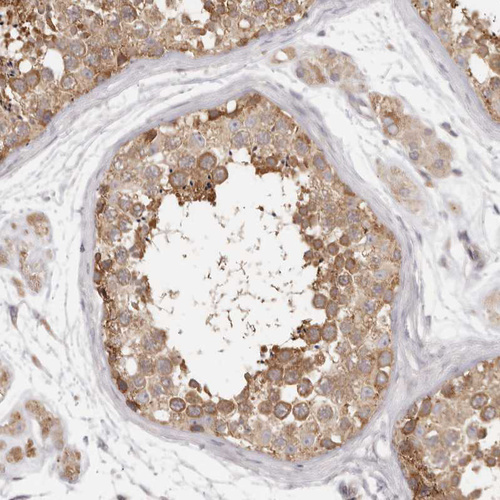

Immunohistochemical staining of human testis shows moderate cytoplasmic positivity in cells in seminiferous ducts.